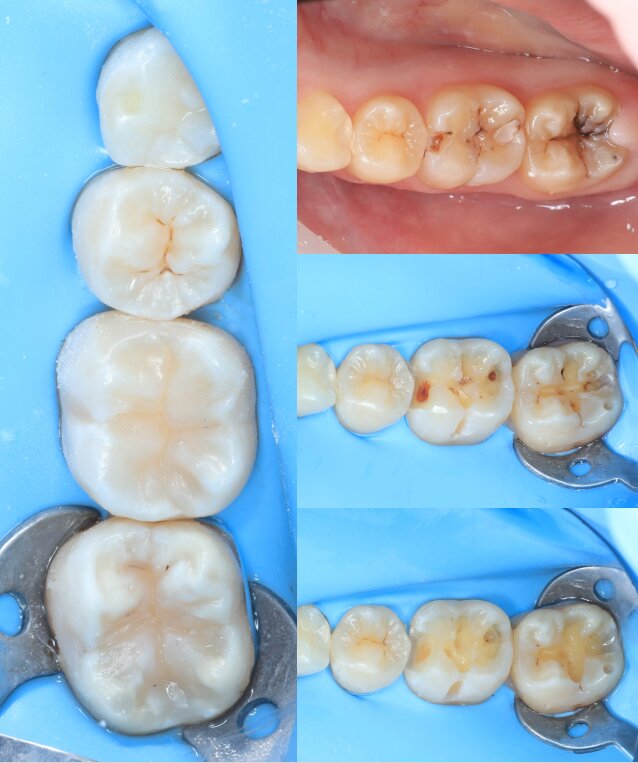

Портфоліо лікаря

У портфоліо представлені реальні клінічні випадки з практики лікаря — від первинного стану до результату лікування. Кожен кейс демонструє індивідуальний підхід, сучасні методи лікування та увагу до деталей